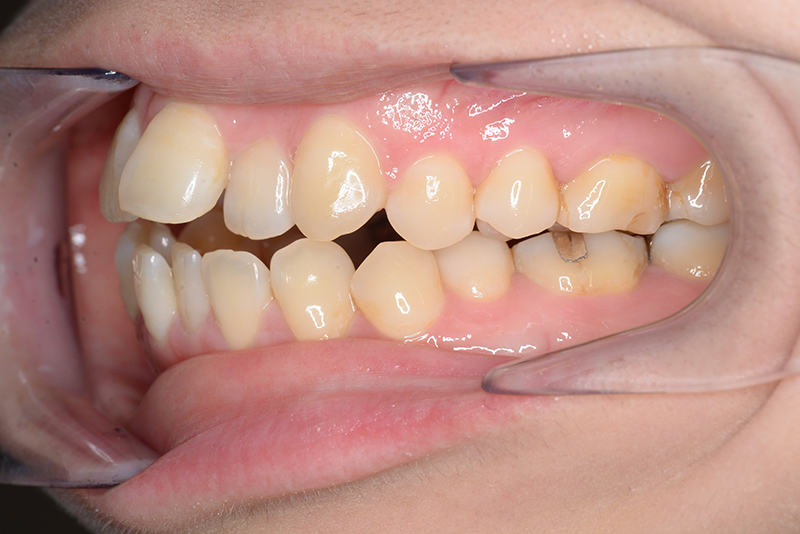

| 主訴 | 前歯で物が噛めない | 診断名 | アングルⅠ級開咬症例 | ||||

|---|---|---|---|---|---|---|---|

| 初診時年齢 | 37歳8ヵ月 | 性別 | 女 | 動的治療期間 | 23ヵ月 | ||

| 口腔内所見 | 臼歯関係はⅠ級、over jet 4.5mm、over bite -3.0mm。上下顎切歯部に軽度の叢生が認められ唇側傾斜をしつつ開咬を呈していた。 |

| 批評・予后 | 治療後において下顎角の開大も認められず歯軸の整直、咬合の緊密化が得られた。また上下顎前歯の後退と共に口元の突出感と口唇閉鎖不全の改善が認められた。 |